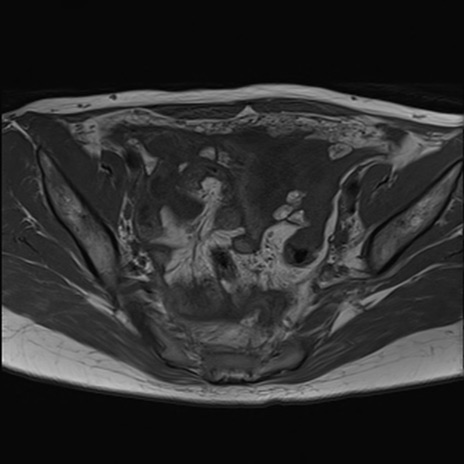

症例39 T1WI(横断像)

MRI(4日後)